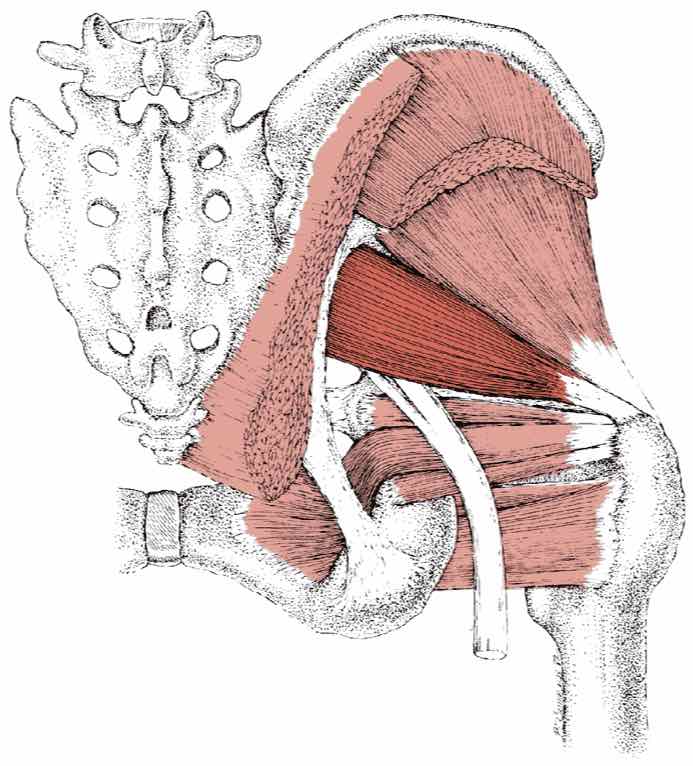

Анатомия мышц: Пириформис

:background_color(FFFFFF):format(jpeg)/images/article/die-hintere-hueftmuskulatur/G5mIfxL7N0ozMPCfEVmg_M._piriformis.png)